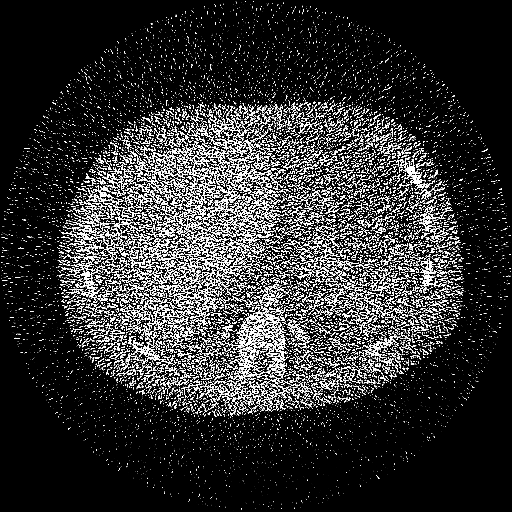

(20-cm cylindrical phantom)